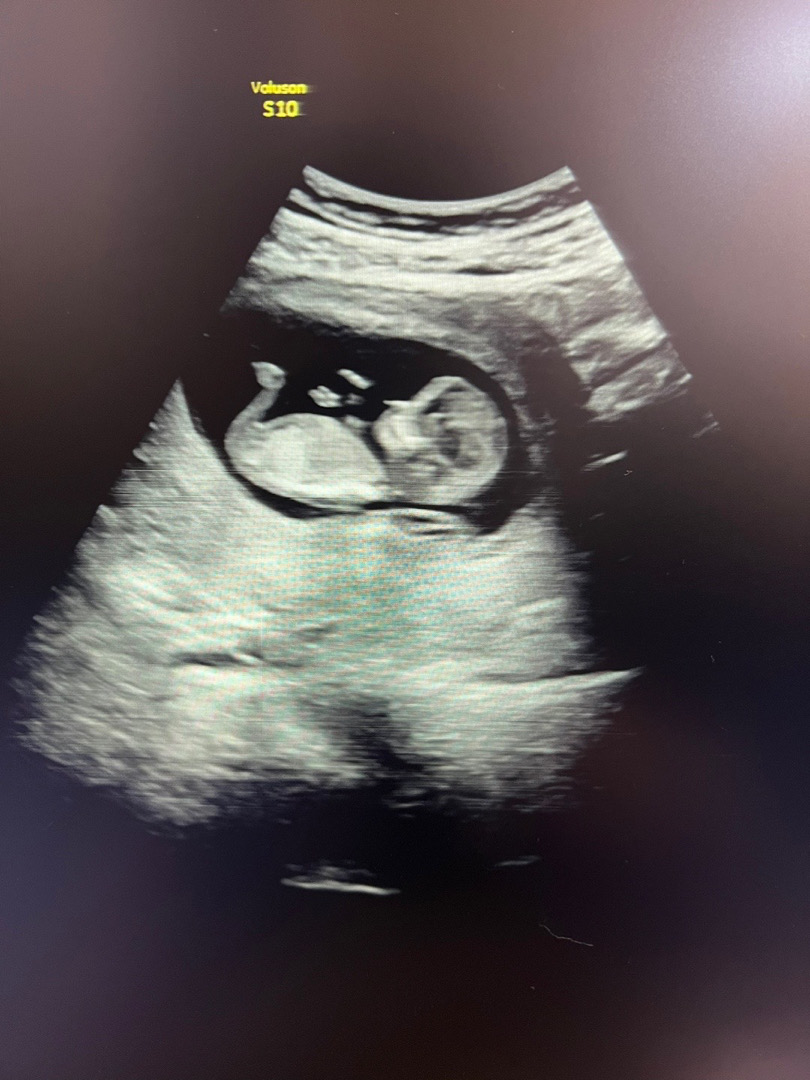

딸 ?! 아들?! 12주 촘파입니당

이걸론 확인 어렵겟죠..?